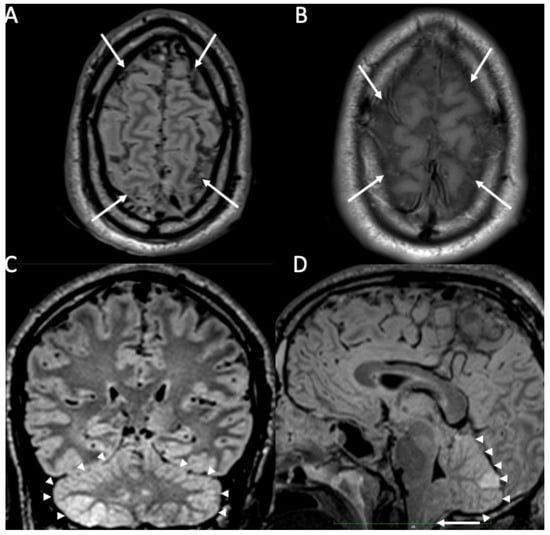

| Piogenic Meningitis | • Cerebrospinal fluid hyperintensity in T1 and FLAIR • Restricted diffusion of the subarachnoid spaces • Meningeal enhancement on T1 and FLAIR |

2. Piogenic Meningitis

3. Tuberculous Meningitis/Meningoencephalitis